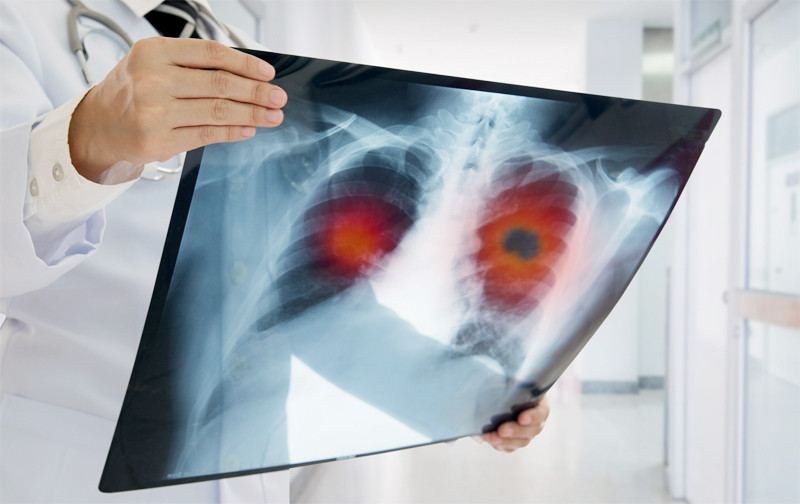

Các dấu hiệu của ung thư phổi thường không đặc hiệu, khó phát hiện và dễ nhầm lẫn với những bệnh lý khác nên nhiều người bệnh đã bỏ lỡ giai đoạn vàng điều trị.

Ung thư phổi không chỉ tác động tới đường hô hấp mà còn bộc lộ triệu chứng trên khuôn mặt, ngón tay của người bệnh.